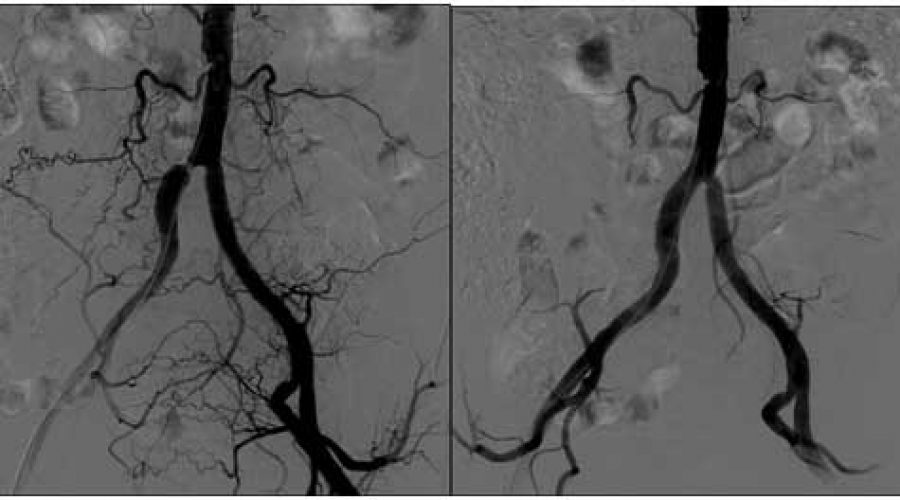

Erkeklerde cinsel damar tıkanıklığı belirtileri. Peki damar tıkanıklığı belirtileri nelerdir damar tıkanıklığı tedavisi nasıl olur. Damar tıkanıklığının pek çok nedeni vardır. Damar tıkanıklığı ile baş etmek için mutlaka sağlıklı beslenme tarzı tercih edilmelidir. örneğin erkeklerde penisi besleyen karındaki aorta ve iliak damarların tıkanıklığı başta penisin sertleşmemesi ile kendini belli eden iktidarsızlık belirtileri oluşturabilir.

üreme organlarındaki damarlarda tıkanıklık. Damar tıkanıklığı kalpte ise ritim bozukluğu kalp bölgesinde ağrı beyinde damar tıkanıklığı var ise görme konuşma bozukluğu hafıza kaybı baş ağrısı bacaklarda damar tıkanıklığında yürürken ve dinlenirken ağrı ayakta deride kangren. Damar tıkanıklığı bacakta meydana gelebildiği gibi üroloji damar tıkanıklığı da nadiren söz konusu olabilir. Erkeklerde testis penis gibi üremeyi sağlayan bölgelere giden kan akımında azalma olursa üreme durumu bundan etkilenir.